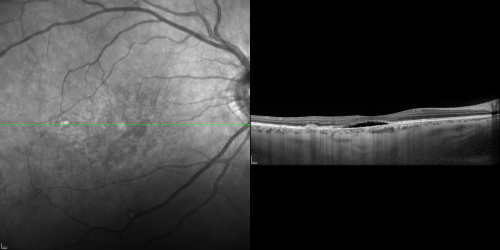

Cuticular Drusen (Basal Laminar Drusen) and Bilateral Chronic Subfoveal Fluid (Serous Retinal Detachment) unresponsive to monthly Avastin OCT OD

66-year-old man with bilateral subfoveal fluid unresponsive to one year of monthly avastin therapy.

OD 20/160,  Pinhole 20/80.   OS 20/63,  Pinhole 20/50.  OCT scan shows subretinal fluid with normal choroidal thickness.  Fluorescein angiogram shows cuticular/basal laminar drusen.  ICG shows no foci of choriocapillaris leakage.